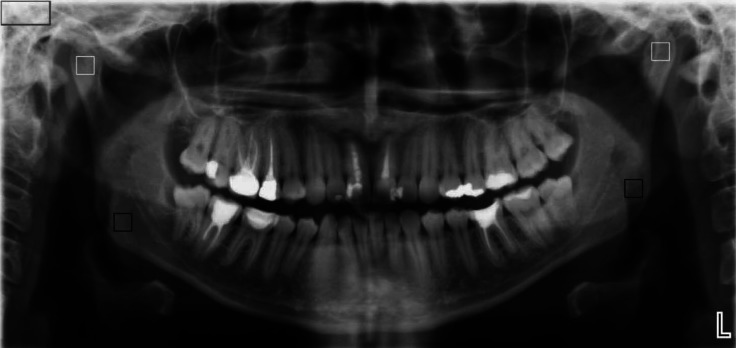

Materials and methods: The study comprised 186 participants, including 144 women and 42 men. Of these, 93 were patients with RA and 93 were healthy controls. For the RA group, disease duration, laboratory findings, and medication use were recorded. Measurements of fractal dimension (FD), lacunarity (Lac), bone area fraction (BA/TA), and trabecular thickness (Tb.Th) were taken at the mandibular condyle and angle. These measurements were obtained from panoramic radiographs using ImageJ version 1.52p (National Institutes of Health, Bethesda, MD, USA).

Results: Relative to control participants, patients with RA exhibited higher FD values for both mandibular condyle and angle regions (P<0.05). Conversely, the RA group displayed lower Lac values for both regions (P<0.05). Similarly, Tb.Th values were significantly lower in the RA patient group for both the condyle and the angle (P<0.05). Furthermore, a significant negative correlation was identified between disease duration and FD at the mandibular condyle (P<0.05).

Conclusion: The results demonstrate that FA can be used to quantitatively assess changes in trabecular bone in the jawbones of patients with RA. Image analysis parameters derived from panoramic radiographs, including FA, Lac, BA/TA, and Tb.Th, hold promise in guiding patients with RA toward appropriate medical examinations.